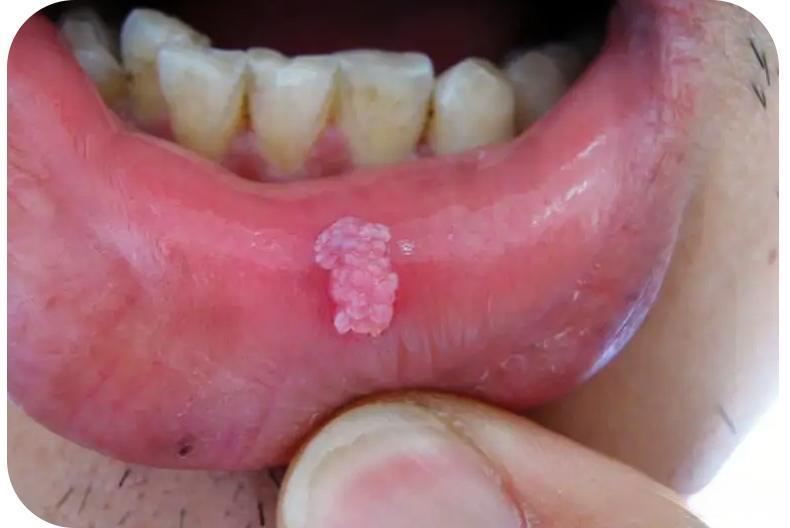

口腔尖锐湿疣的典型症状包括:病变多位于舌系带及其附近,皮疹隆起呈乳头状、菜花状、鸡冠状或鹅卵石样外观,绿豆至蚕豆大小,边界清楚,数目1~10个不等。皮疹颜色多呈淡红色或鲜红色,触之易出血。在显微镜下,可见表皮呈弥漫性角化不全,并呈乳头瘤样增生,棘细胞明显肥厚,可见空泡细胞,真皮浅部毛细血管扩张及慢性炎症细胞浸润。